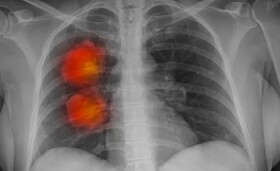

سه عامل نیمی از مرگ و میرهای ناشی از سرطان در جهان

نتایج یک مطالعه نشان می دهد: استعمال سیگار و سایر عوامل خطرزا، عامل تقریبا نیمی از مرگ و میرهای ناشی از سرطان است.

به گزارش ایسنا، بر اساس نتایج مطالعه متخصصان آمریکایی، استعمال سیگار، مصرف مواد الکلی، اضافه وزن و سایر عوامل خطرزا عامل تقریبا نیمی از مرگ و میرهای ناشی از سرطان در سراسر جهان هستند.

سرطان دومین عامل مرگ و میر در جهان است و قرار گرفتن در معرض عوامل خطر نقش کلیدی در بیولوژی و بار بسیاری از انواع سرطان ایفا می کند. پزشکان دلایل دقیق ابتلا به سرطان را نمی ‌دانند اما عوامل خطری وجود دارد که می ‌تواند احتمال ابتلای افراد به آن را افزایش دهد.

اکنون گروهی از متخصصان آمریکایی چگونگی تاثیر عوامل خطر در مرگ و میر ناشی از سرطان را در سطح جهان بررسی کردند. استعمال دخانیات، مصرف مواد الکلی و شاخص توده بدنی بالا (BMI) بزرگترین عوامل موثر در این موضوع هستند. در مجموع، عوامل خطرزا عامل تقریبا ۴.۴۵ میلیون مرگ ناشی از سرطان در سال هستند.

به گفته متخصصان، این آمار نشان دهنده ۴۴.۴ درصد از کل مرگ و میر ناشی از سرطان در سراسر جهان است. نیمی از مرگ و میرهای ناشی از سرطان در میان مردان در سال ۲۰۱۹ به دلیل عوامل خطرزا بوده و در زنان بیش از یک سوم مجموع مرگ و میرهای ناشی از سرطان تحت تاثیر این عوامل بوده است.